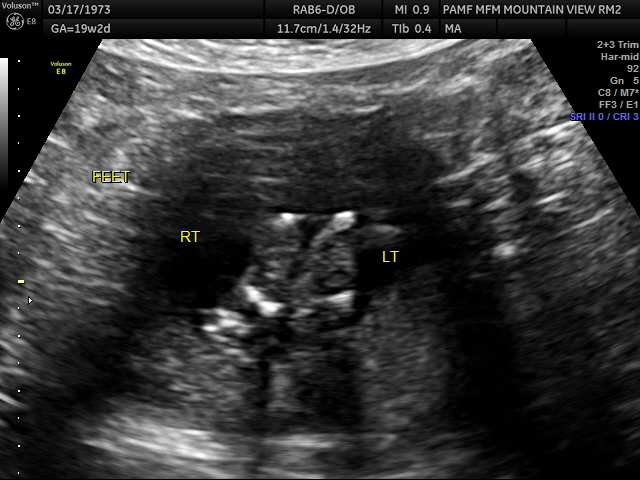

This week I had two baby related appointments. The first was was Maternal Fetal Medicine and has many names. It’s known as a 20 week scan though it’s possible to have it done from 18 – 20 weeks 6 days, an anatomy scan, a detail scan and in some places and countries the anomaly scan. To me calling it the detail scan makes lots of sense as they do take many pictures of details of the bay including this one which is the feet, which I wouldn’t have been able to figure out for posting purposes had it not been labeled for me.